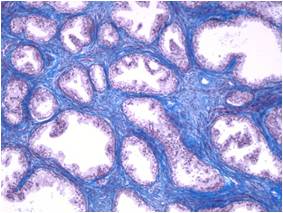

■ Examples of applications

Fluorescence in-situ hybridization (FISH) of an endothel cell.